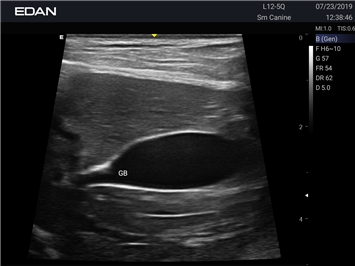

Новая эра УЗИ в ветеринарии. Диагностическая ультразвуковая система для ветеринарии, AX8 — это многофункциональная диагностическая ультразвуковая платформа с расширенными режимами визуализации, двумя сенсорными экранами с жестовым управлением и полным набором датчиков, которые соответствуют конкретным потребностям ветеринаров.

Профессиональный ветеринарный УЗИ аппарат EDAN Acclarix AX8 VET сочетает инновационные технологии визуализации с надежной конструкцией, специально разработанной для ветеринарной практики.

Цветовой допплер:

Да

B-режим, Двухмерное сканирование: